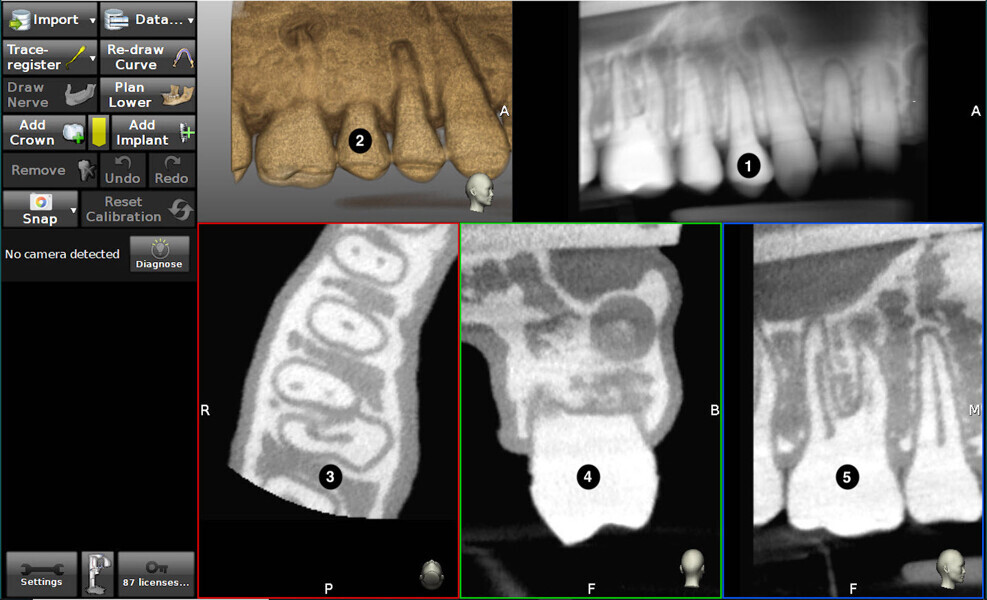

Fig. 3: The screen is divided into (1) panoramic view, (2) 3D reconstruction, (3) axial view, and (4) buccolingual and (5) mesiodistal section views.